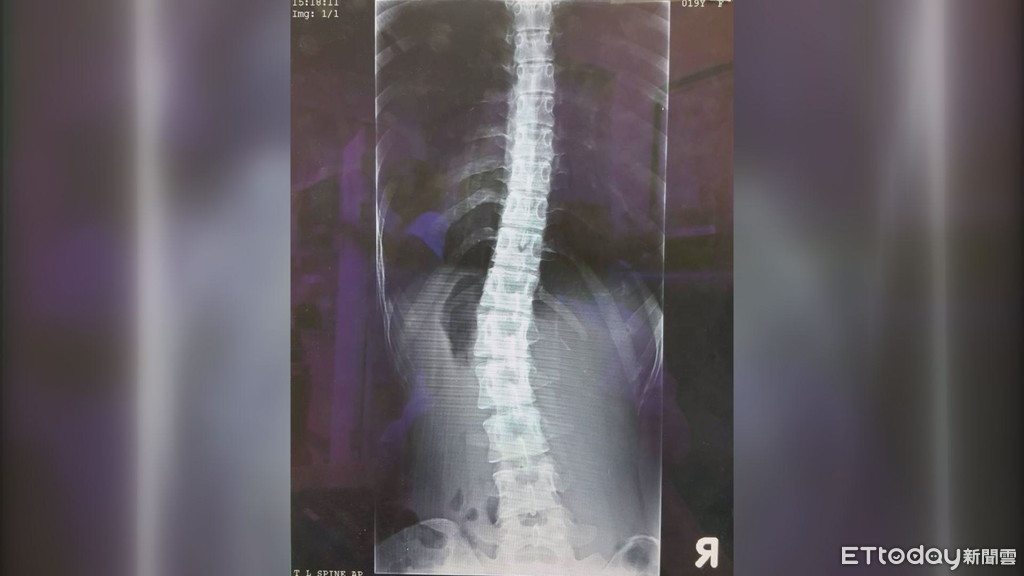

▲戴姓女子因經常腰痠背痛,長期忽視脊椎側彎的問題,就醫檢查發現,已惡化並彎曲到25度,恐影響心肺功能。(圖/記者黃孟珍翻攝)

苗栗後龍診所復健科醫師陳泰安表示,正常的脊椎由背面看應該是呈直線的,如有向左或向右成C型或S型彎曲,就稱作脊椎側彎。而戴姓女子因受背痛所苦到診所就醫,經X光檢查發現,脊椎側彎角度達25度,經醫師及物理治療團隊治療後,側彎角度已縮減至15度,原來的疼痛感也逐漸消失。